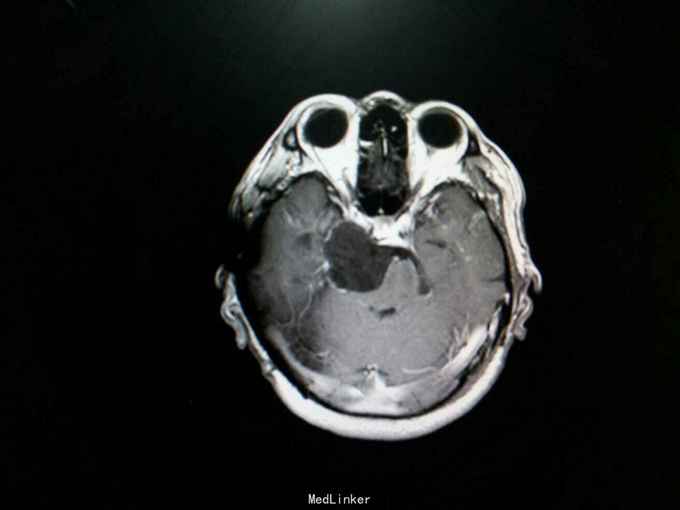

查体:生命体征平稳。神经系统检查:右侧眼睑下垂,左侧眼睑无下垂。肌力 右侧肢体肌力5-级,左侧肢体肌力正常。肌张力: 右上肢肌张力正常,右下肢肌张力正常;左上肢肌张力正常,左下肢肌张力正常。肌营养检查:四肢肌肉无萎缩。共济与平衡检查:正常。外院颅脑CT示右侧桥脑小脑角团片囊性低密度区,性质待定,蝶窦右后方局部骨质缺损代之稍低密度软组织肿块,考虑原肿瘤复发,颅骨呈术后改变,颅脑CT增强示颅内占位性病变(表皮样囊肿?)。入院后行颅脑MRI检查提示: 右侧颞骨岩尖-脚间池-右侧环池-右侧桥小脑角池见片状异常信号影,边界清,形态不规则,呈匍匐状分布,冠状位范围约47mm×29mm。相应右侧颞、脑干明显受压,脑干向左移位。第三脑室略向左移位。右侧额骨、颞骨骨皮质欠连续,呈术后改变。 考虑右侧颞骨岩尖-脚间池-右侧环池-右侧桥小脑角池表皮样囊肿。 右侧颅骨呈术后改变。

诊断:右中后颅窝表皮样囊肿 处理:幕上下联合入路右中后颅窝表皮样囊肿切除术